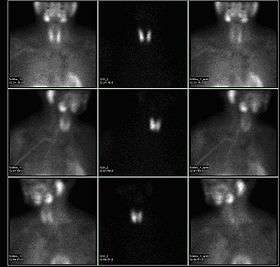

A nuclear medicine parathyroid scan demonstrates a parathyroid adenoma adjacent to the left inferior pole of the thyroid gland. The above study was performed with Technetium-Sestamibi (1st column) and iodine-123 (2nd column) simultaneous imaging and the subtraction technique (3rd column).